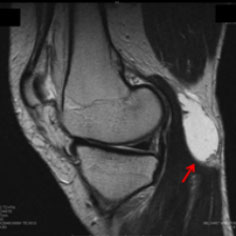

脊柱管狭窄症とは、脊髄の通り道である脊柱管が狭くなることで神経が圧迫され、痛みやしびれが生じる疾患です。脊柱管は脊椎によって形成されるトンネル状の空間で、脊髄や神経根が通っています。加齢や変性によって骨や靱帯が肥厚し、脊柱管が狭くなることが一般的な原因です。症状は部位によって異なりますが、腰部に発生することが多く、主な症状としては腰痛、足のしびれや痛み、歩行困難(間欠性跛行)などがあります。

脊柱管狭窄症の主な原因は、加齢による脊椎の変性です。椎間板のすり減りや、椎間関節の肥大、靱帯の肥厚が進行し、脊柱管が狭くなります。また、外傷や先天性の要因、骨の病変が影響することもあります。特に60歳以上の高齢者に多く見られますが、若年層でも外傷や特定の疾患により発症することがあります。